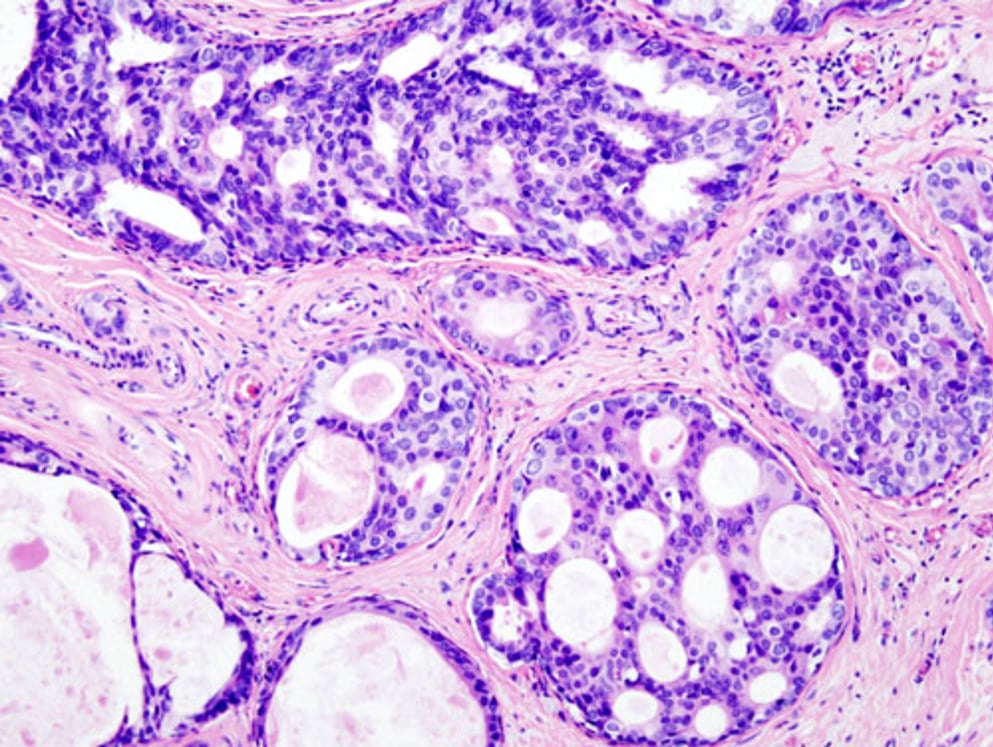

Фотографии опухоли медуллярной аденокарциномы